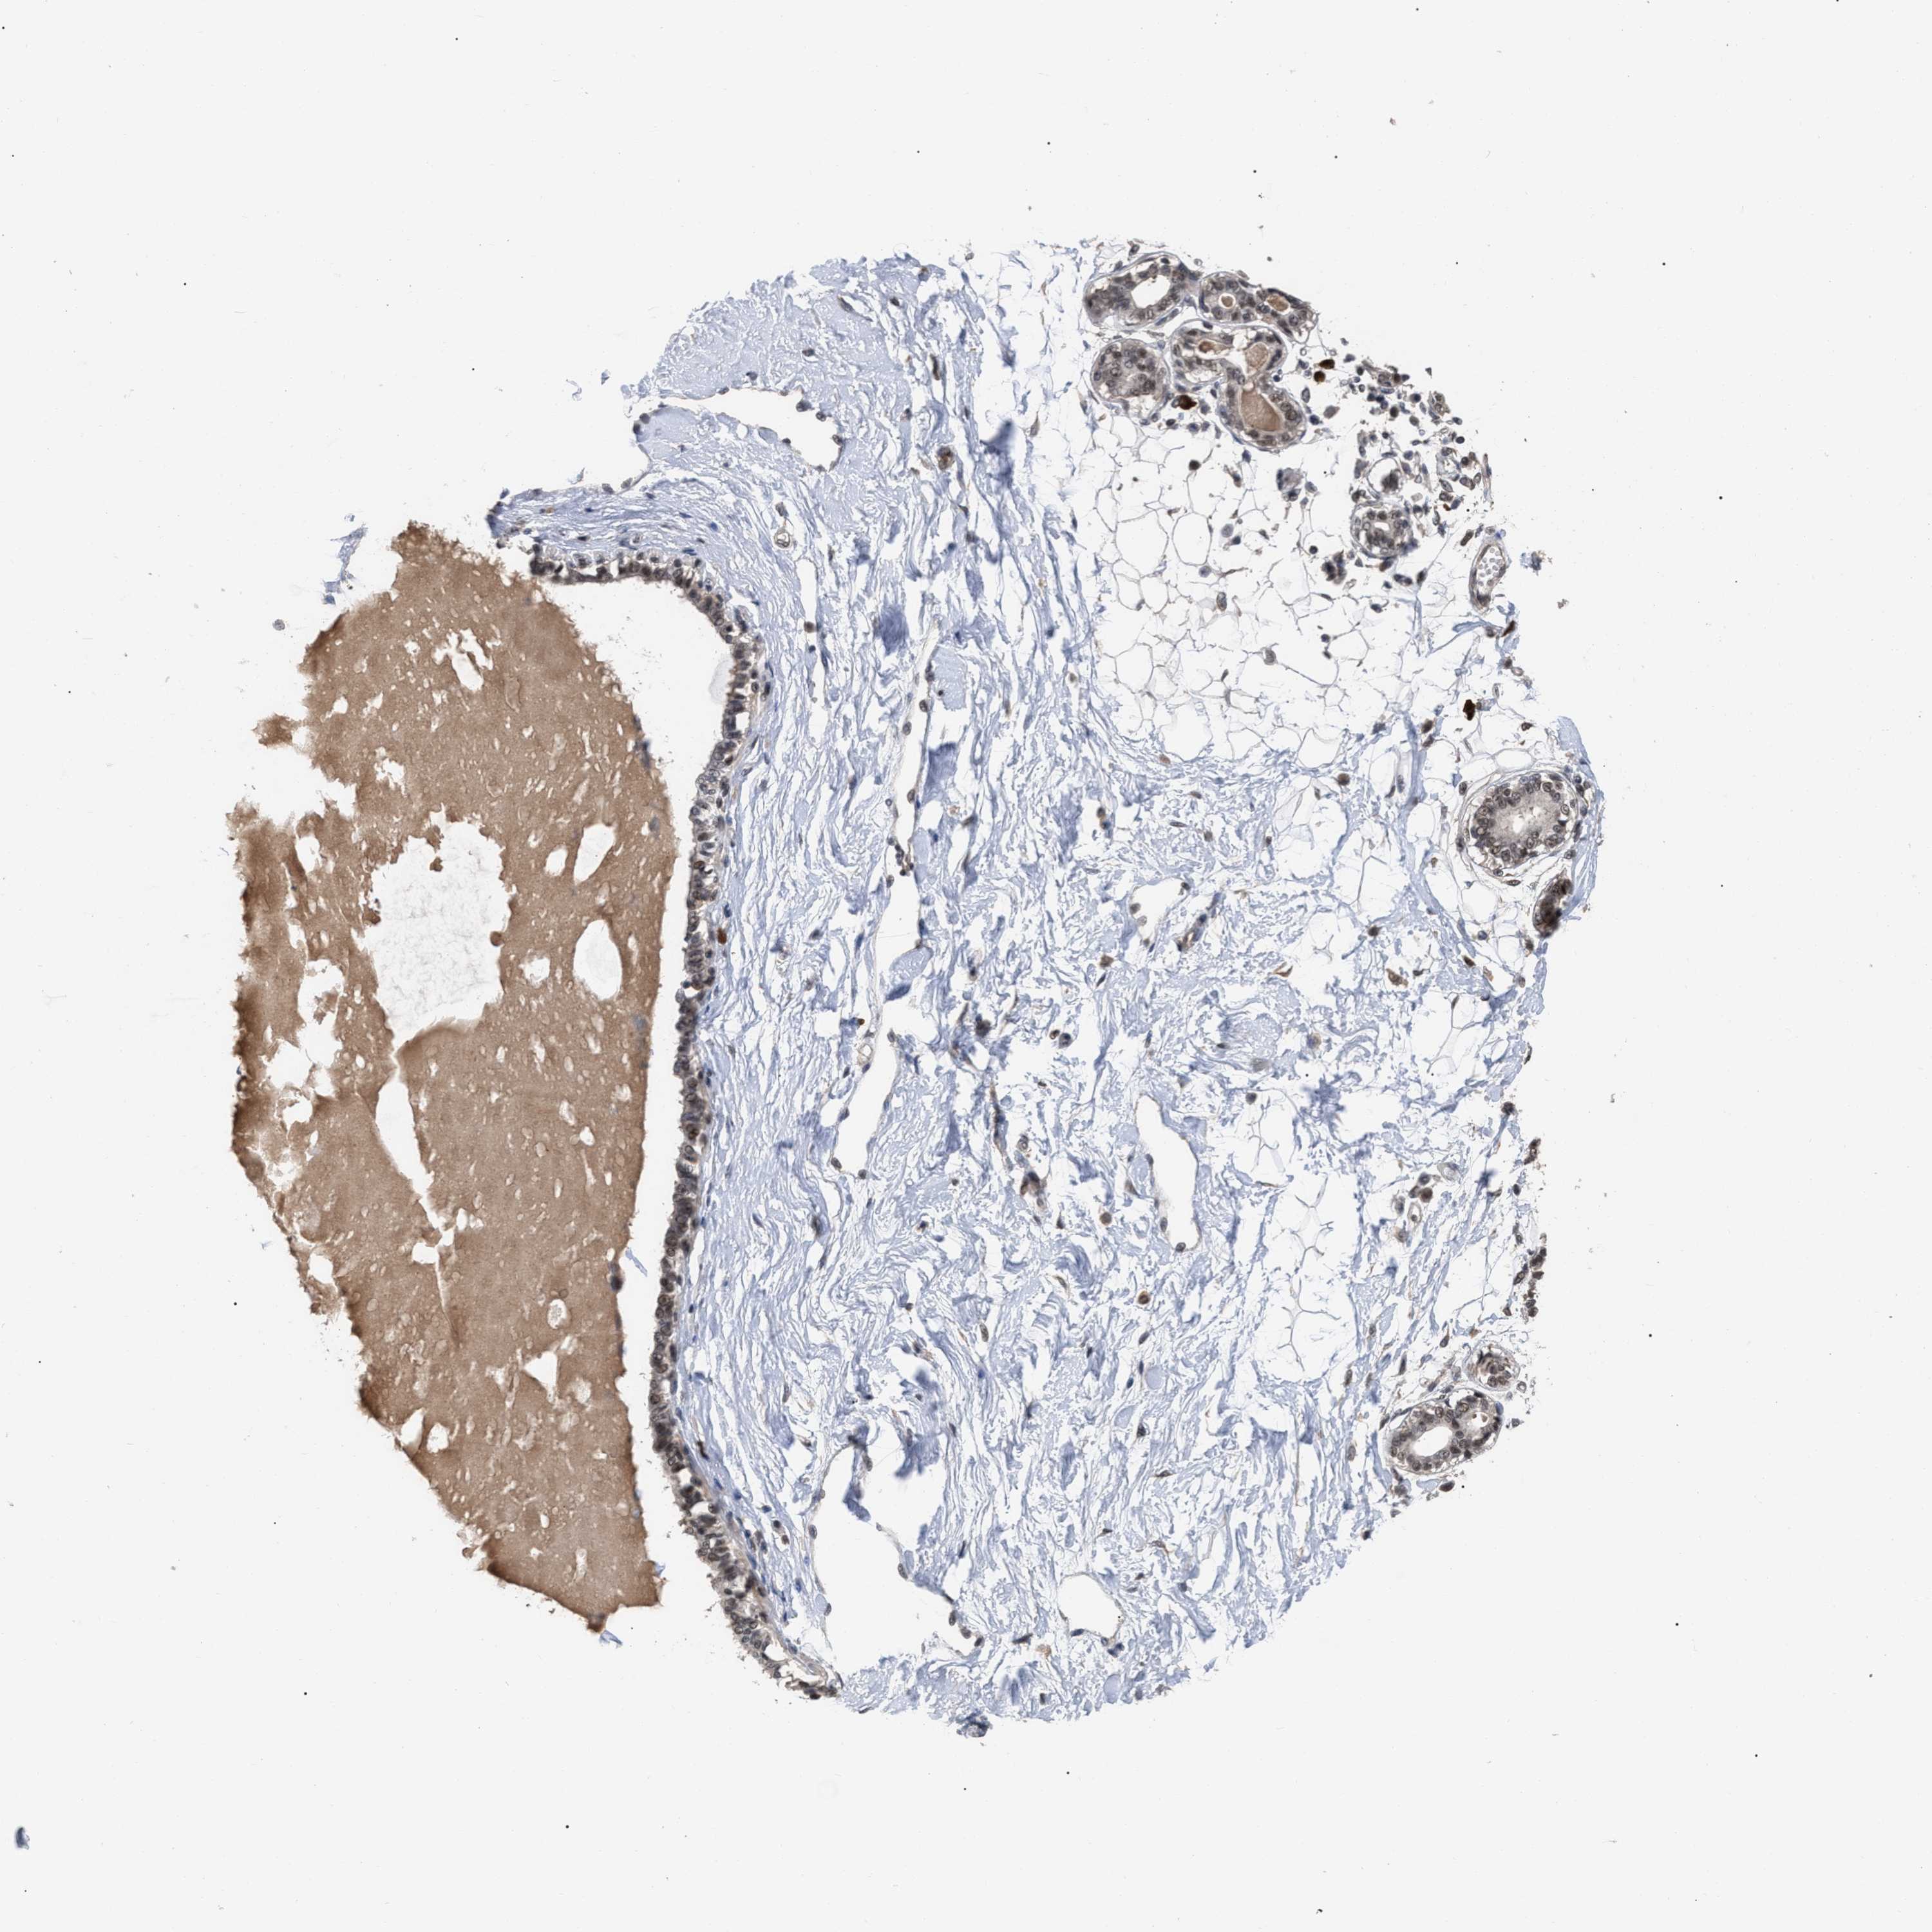

BREAST - Antibody stainingi

Antibody staining in the annotated cell types in the current human tissue is reported as not detected, low, medium, or high, based on conventional immunohistochemistry profiling in selected tissues. This score is based on the combination of the staining intensity and fraction of stained cells.

Each image is clickable and will lead to virtual microscopy that enables deeper exploration of all samples and also displays staining intensity scores, fraction scores and subcellular localization as well as patient and tissue information for each sample.

Antibody CAB019271

Adipocytes Low

Glandular cells Low

Myoepithelial cells Low